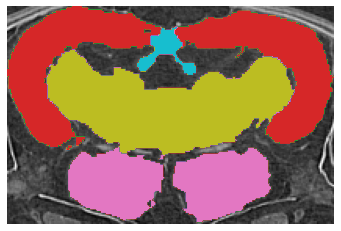

Fig.ย 2: Examples of (a) Input image, (b) ground truth, and segmentation results by (c) the Teacher (Fully Supervised), (d) the Student model by the proposed method.

First, we present a quantitative comparison of the results of the proposed method with the Fully Supervised model as a baseline in Tableย 1. The proposed method clearly outperforms the baseline in both the low and full data regimes. These results demonstrate that our method consistently outperformed the baseline. In addition, the proposed method using only seven labeled volumes provided better performance than the baseline using all available training data volumes, confirming the proposed method can improve the Medaka segmentation performance. Remarkably, our method using only two volumes of the labeled data achieved better results than the Fully Supervised method with 12 labeled volumes. Second, we visually compare the results of the segmentation as shown in Fig.ย 2. We marked the problematic areas of the sample with yellow circles in Fig.ย 2 (c). While the prediction of the proposed method clearly has its own peculiarities of segmentation, the provided result is smoother spatially and closer to the ground truth.